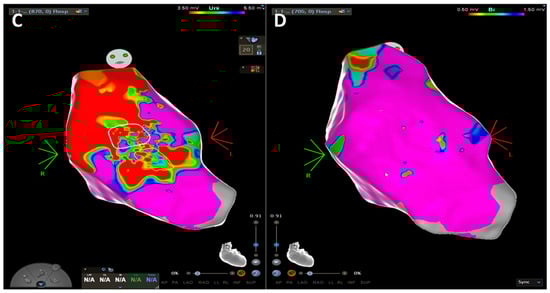

In sudden cardiac death risk evaluation, three-dimensional electroanatomic voltage mapping (EVM) offers the potential to identify the presence, location, and extent of the pathological substrate of ACM by detection of low-voltage areas that correspond to regions of RV myocardial loss and fibrofatty replacement [76]. Corrado et al. tested the hypothesis that RV electroanatomic low-amplitude areas were significantly associated with the histopathological finding of myocyte loss and fibrofatty replacement in endomyocardial biopsy [76]. This peculiar pathological process leads to islets of residual myocytes interspersed among adipocytes and fibrous tissue, providing an ideal milieu for re-entrant VT [77]. Similarly, case series suggested that low-voltage areas on invasive EVM could identify ACM at an earlier stage as compared to LGE and fatty infiltration on CE-CMR [78].

This “electroanatomic scar” area is defined as an area ≥ 1 cm2, including at least three adjacent points with bipolar signal amplitude < 0.5 mV. The color display for depicting normal and abnormal voltage myocardium ranges from “red” representing “electroanatomic scar tissue” (amplitude < 0.5 mV) to “purple” representing “electroanatomic normal tissue” (amplitude ≥ 1.5 mV). Intermediate colors represent the “electroanatomic border zone” (signal amplitudes between 0.5 and 1.5 mV) (1,3). A relatively sharp border, as identified by a steep spatial voltage gradient, could be used to demarcate the dysplastic regions. Unipolar voltage (UV) mapping of RV endocardium has been explored to predict the disease and the epicardial arrhythmogenic substrates. Evaluation of the epicardial abnormal substrates can be achieved using the RV endocardial unipolar voltage mapping with a cut-off value of 5.5 mV, and the abnormal area is correlated to the epicardial scar in ACM, although the different cut-off value of 4.4 mV has been proposed through the site-by-site comparison [79]. The previous studies based on CE-CMR imaging also supported that the bipolar low-voltage area and the territories displaying abnormal EGMs were correlated to the transmural scar [79,80]. In addition, even in the absence of an RV scar in CMR, parameters significantly associated with electroanatomic low-voltage areas are right precordial QRS prolongation, low-voltage QRS in the limb leads, and late potentials. Accordingly, intracardiac EGMs recorded from within the electroanatomic RV low-voltage areas often appeared fractionated with significantly prolonged duration and extended beyond the offset of the surface QRS compared with EGMs recorded from normal-voltage areas [78]. Hence, the ability to identify the dysplastic process by the presence of low-amplitude EGMs may be used as a new criterion in these patients’ work-up [75]. Considering the extensive pathological substrate due to the fact that the disease process in ACM initiates from the epicardium toward the endocardium, it is important to emphasize the relevance of a comprehensive and extensive substrate-based ablation strategy that incorporates endocardial (ENDO) and, if still inducible, epicardial (EPI) ablation to achieve the long-term VT control [77]. The 2022 ESC guidelines for the management of patients with ventricular arrhythmias and the prevention of sudden cardiac death recommended (class IIa, level of evidence C) ENDO and adjuvant EPI substrate ablation in patients with ACM and recurrent, symptomatic sustained monomorphic VT (SMVT), ICD shocks for SMVT despite anti-arrhythmogenic drugs or beta-blockers, or persistent inducibility after ENDO-only ablation.

Figure 5.

CE-CMR images in patients with ACM without RV morpho-functional abnormalities and LGE. (A) Short axis two-chamber view. (B) Long axis four-chamber view. (C) RV electroanatomic mapping depicting an epicardial scar on the RV free wall. Unipolar voltage map showing low voltages consistent with an epicardial scar. (D) Bipolar voltage map showing normal voltages.